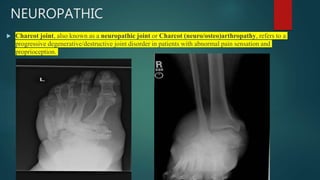

NEUROPATHIC

 Charcot joint, also known as a neuropathic joint or Charcot (neuro/osteo)arthropathy, refers to a

progressive degenerative/destructive joint disorder in patients with abnormal pain sensation and

proprioception.

• #86 There is destruction and deformity of the tarsal bones characterised by sclerosis, joint space narrowing, cortical irregularities, and loose bodies. Lisfranc injury involving the second to fifth tarsometatarsal joints with lateral dislocation. Cortical thickening and sclerosis involving the proximal second to fifth metatarsal bones. Local soft tissue oedema. Destruction, disorganisation and fragmentation of the subtalar and inter-tarsal joints, associated with soft tissue tumefaction and multiple bone fragments.